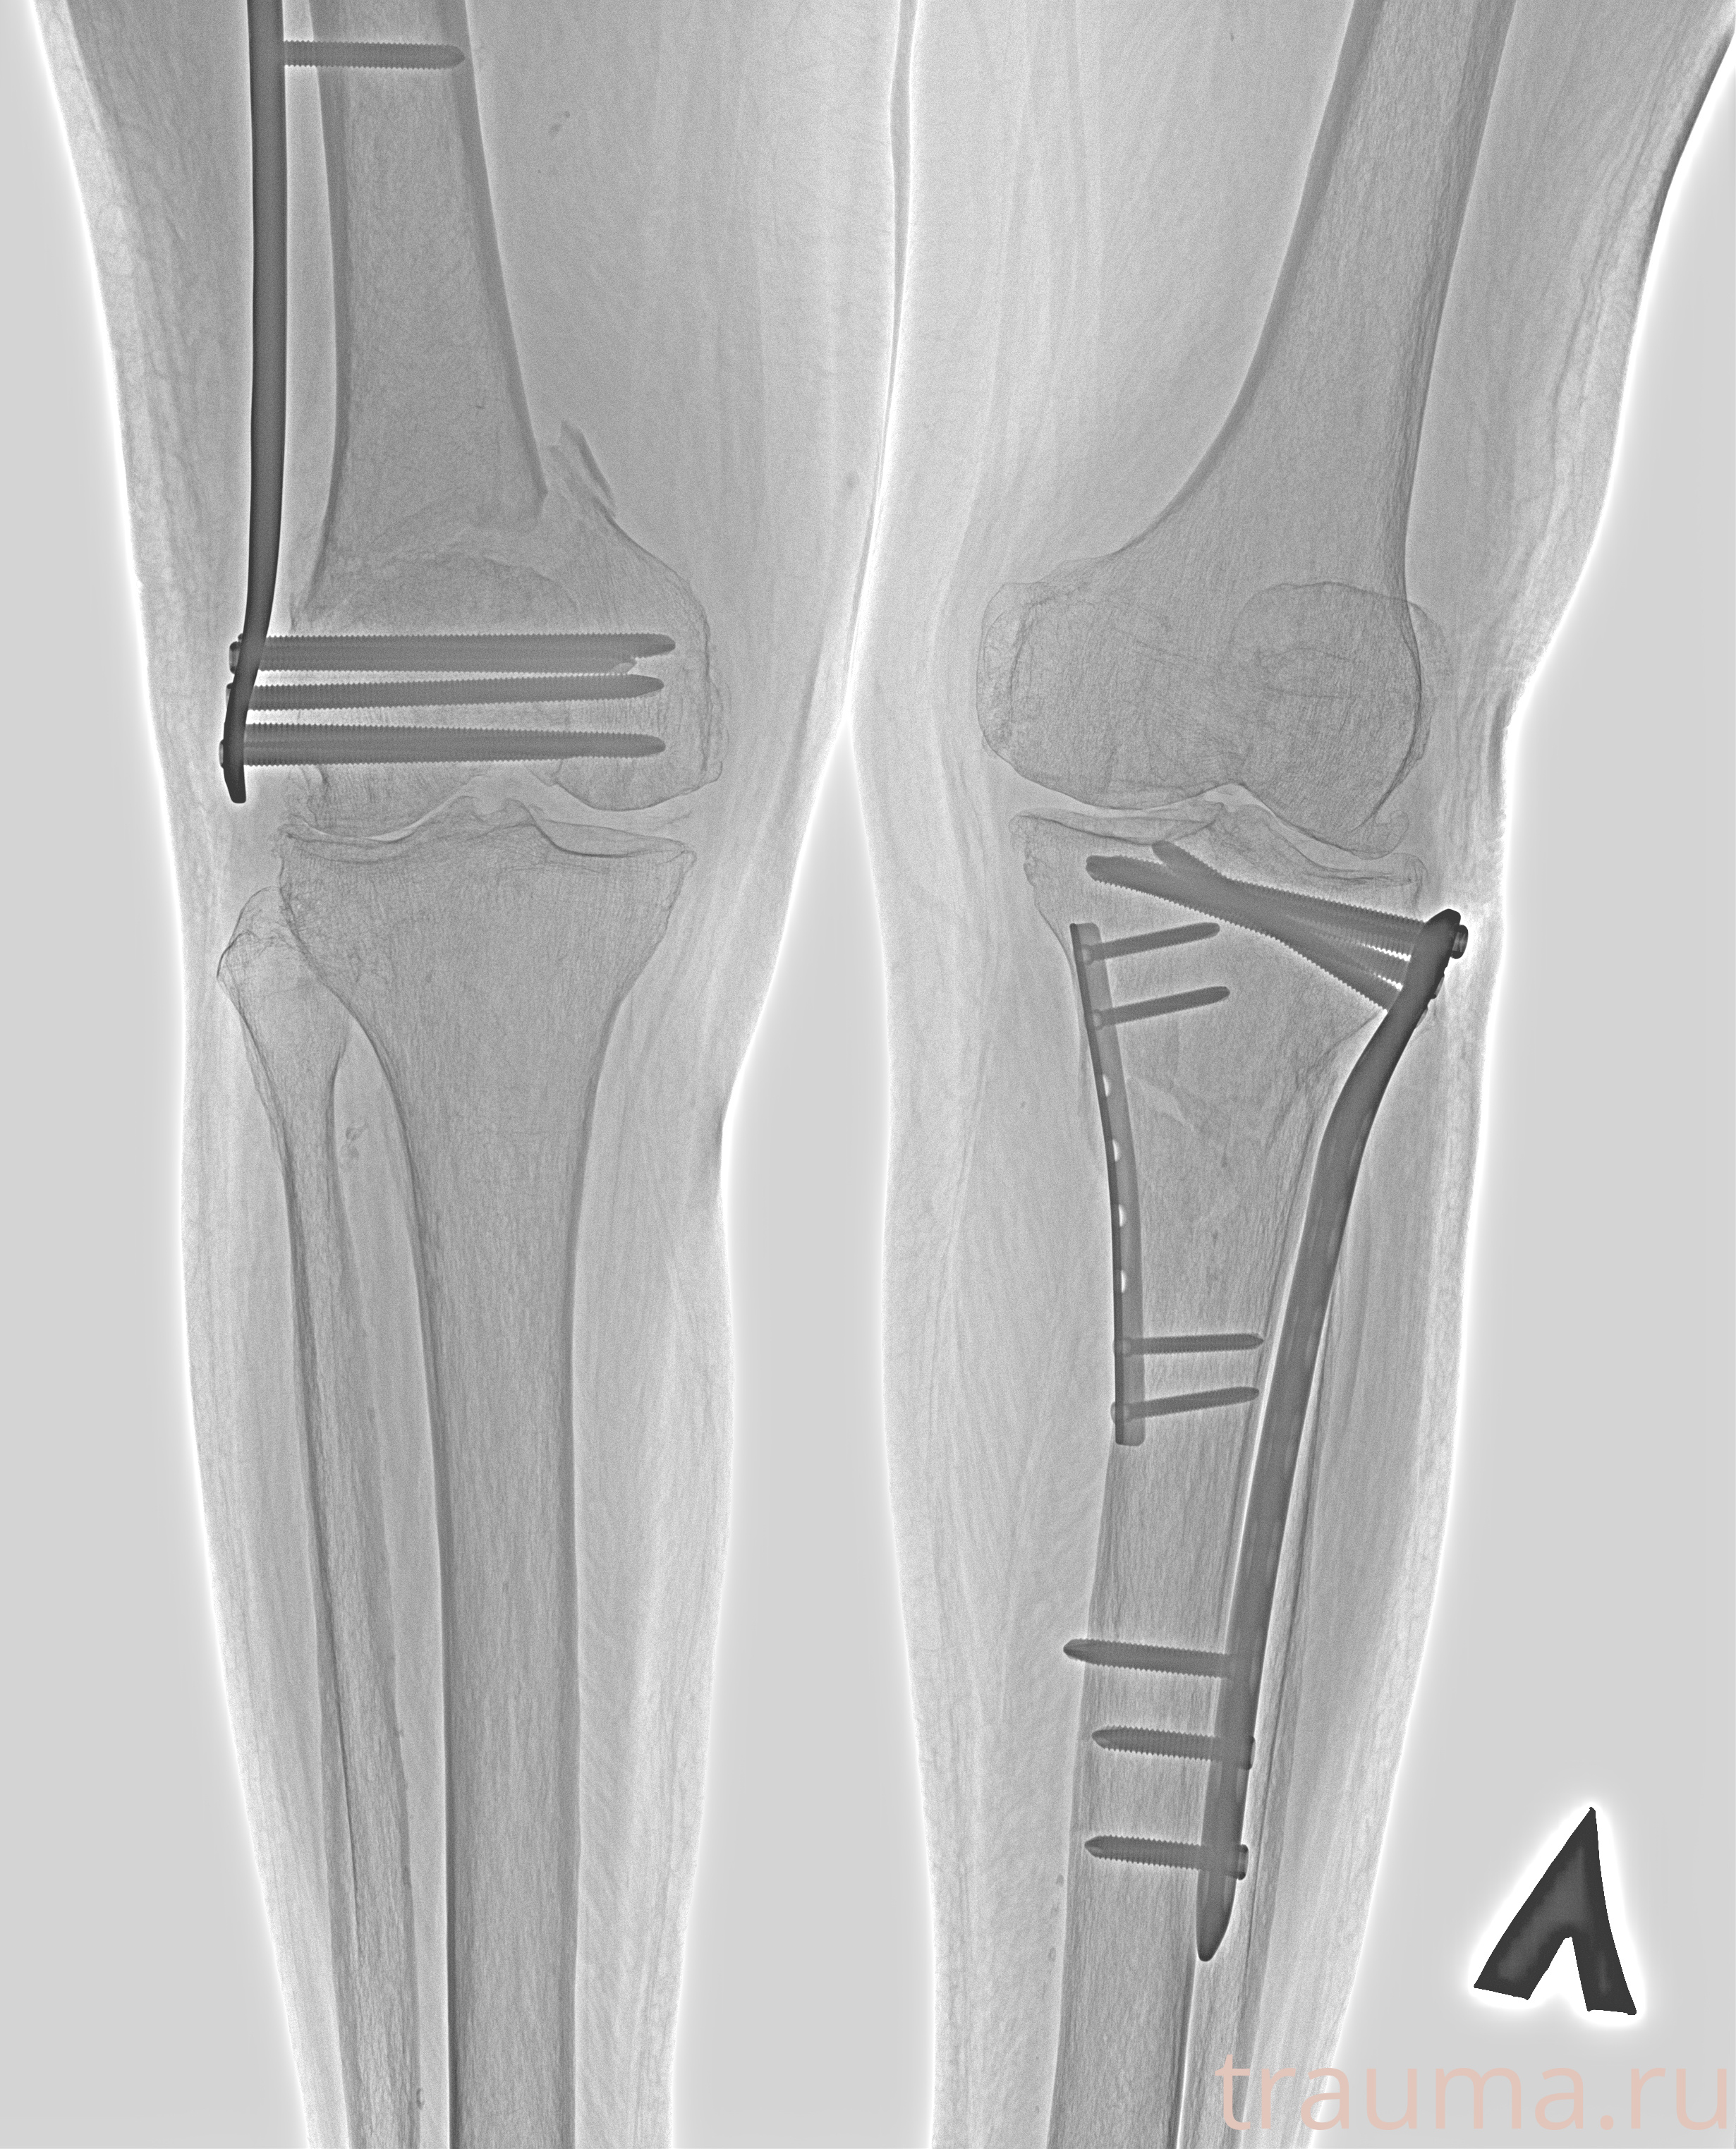

Рентгенограммы

Рентген на дому: по вашему адресу приезжает врач-рентгенолог, травматолог-ортопед с мобильным рентгеновским аппаратом, проводит диагностику травмы или заболевания, делает необходимые рентгенограммы, дает рекомендации по дальнейшему лечению. Получить качественные снимки в домашних условиях возможно благодаря уникальной методике, разработанной МосРентген Центром для института  Склифосовского